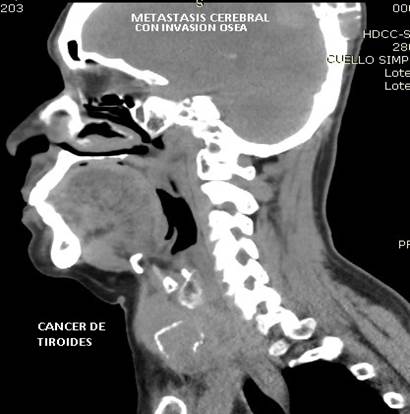

CASO 2 (METASTASIS CEREBRAL)

Paciente de 68 años de edad, que ingresa referida de otra institución por presentar más tumoral en región occipital derecha de gran tamaño dura muy adherida, dolorosa con circulación colateral; paciente desorientada en tiempo y espacio, irritable y poco colaborativa, en algunas ocasiones ha presentado convulsiones tónico clónicas. Además, presenta masa cervical voluminosa, a nivel tiroidea, dura, adherida a estructura aéreas y vasculares.

Se toma biopsia con aguja gruesa de lesión tumoral cervical y tumoración occipital encontrando carcinoma papilar variante oncocitica. Paciente fue tratada por el departamento de oncología clínica en forma paliativa y con Sorafenib por no haber mejoría con radio-yodo.

Ilustración 7 Ca de tiroides vultuoso

![]() |

Fuente: Hospital de Especialidades Guayaquil “Doctor Abel Gilbert Pontón”.

Autor: Dr. Fernando Moncayo A.

Ilustración 8 Ca de tiroides y metástasis cerebral.